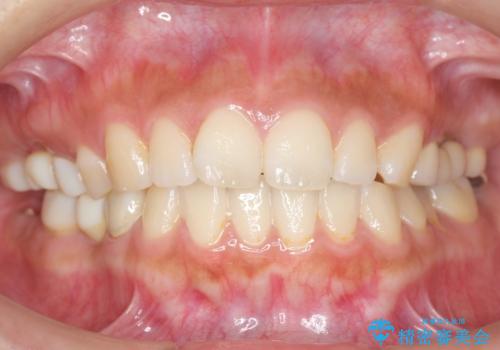

使っていない親知らず(左上8)を左上7抜歯窩に移植し、支台歯としてブリッジによる補綴治療を行いました。

奥歯で咬むことができるようになり、また見た目も自然だと大変喜んで頂けました。

被せ物の種類:メタルボンドクラウン エコノミー フルベイク